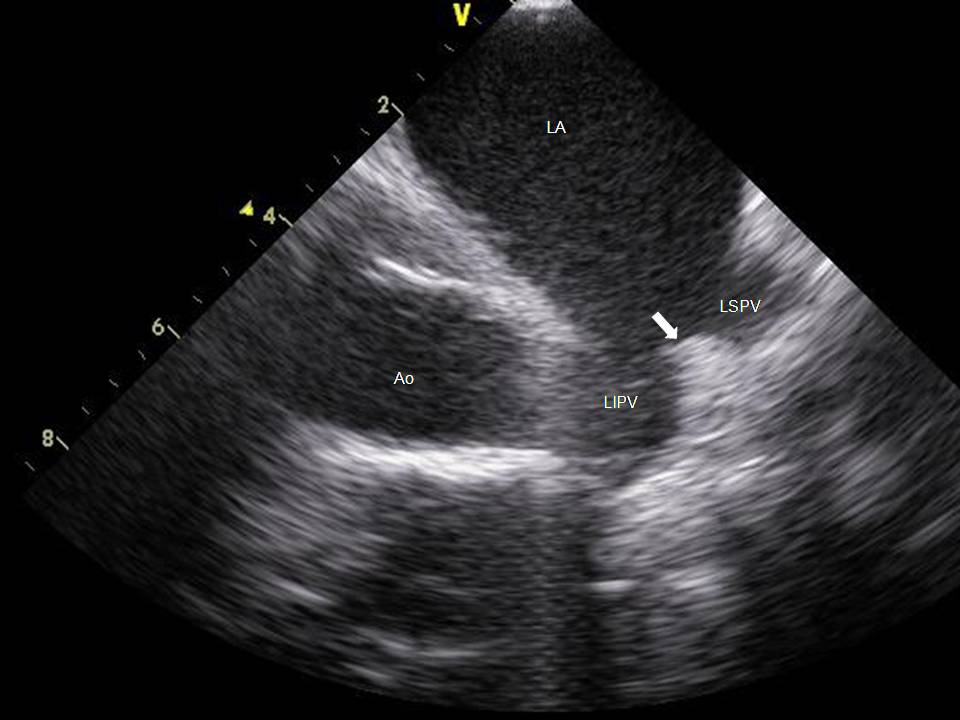

Use of ICE to Eliminate Radiation During AF Ablation

2015-07-24 13:06